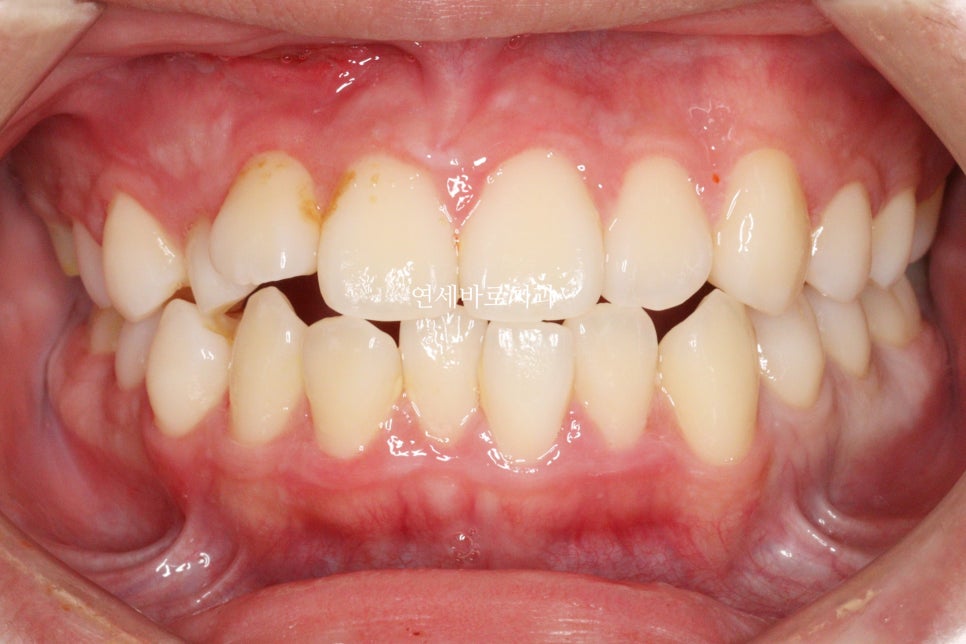

거의 끝나가 아래쪽 장치를 먼저 제거했습니다.

환자가 불편하다고 빨리 끝난 쪽이라도 제거를 먼저하길 원했어요

괜찮아요 먼저 제거해도.

그래서 먼저 제거하고 위쪽을 조금 더 진행했습니다.